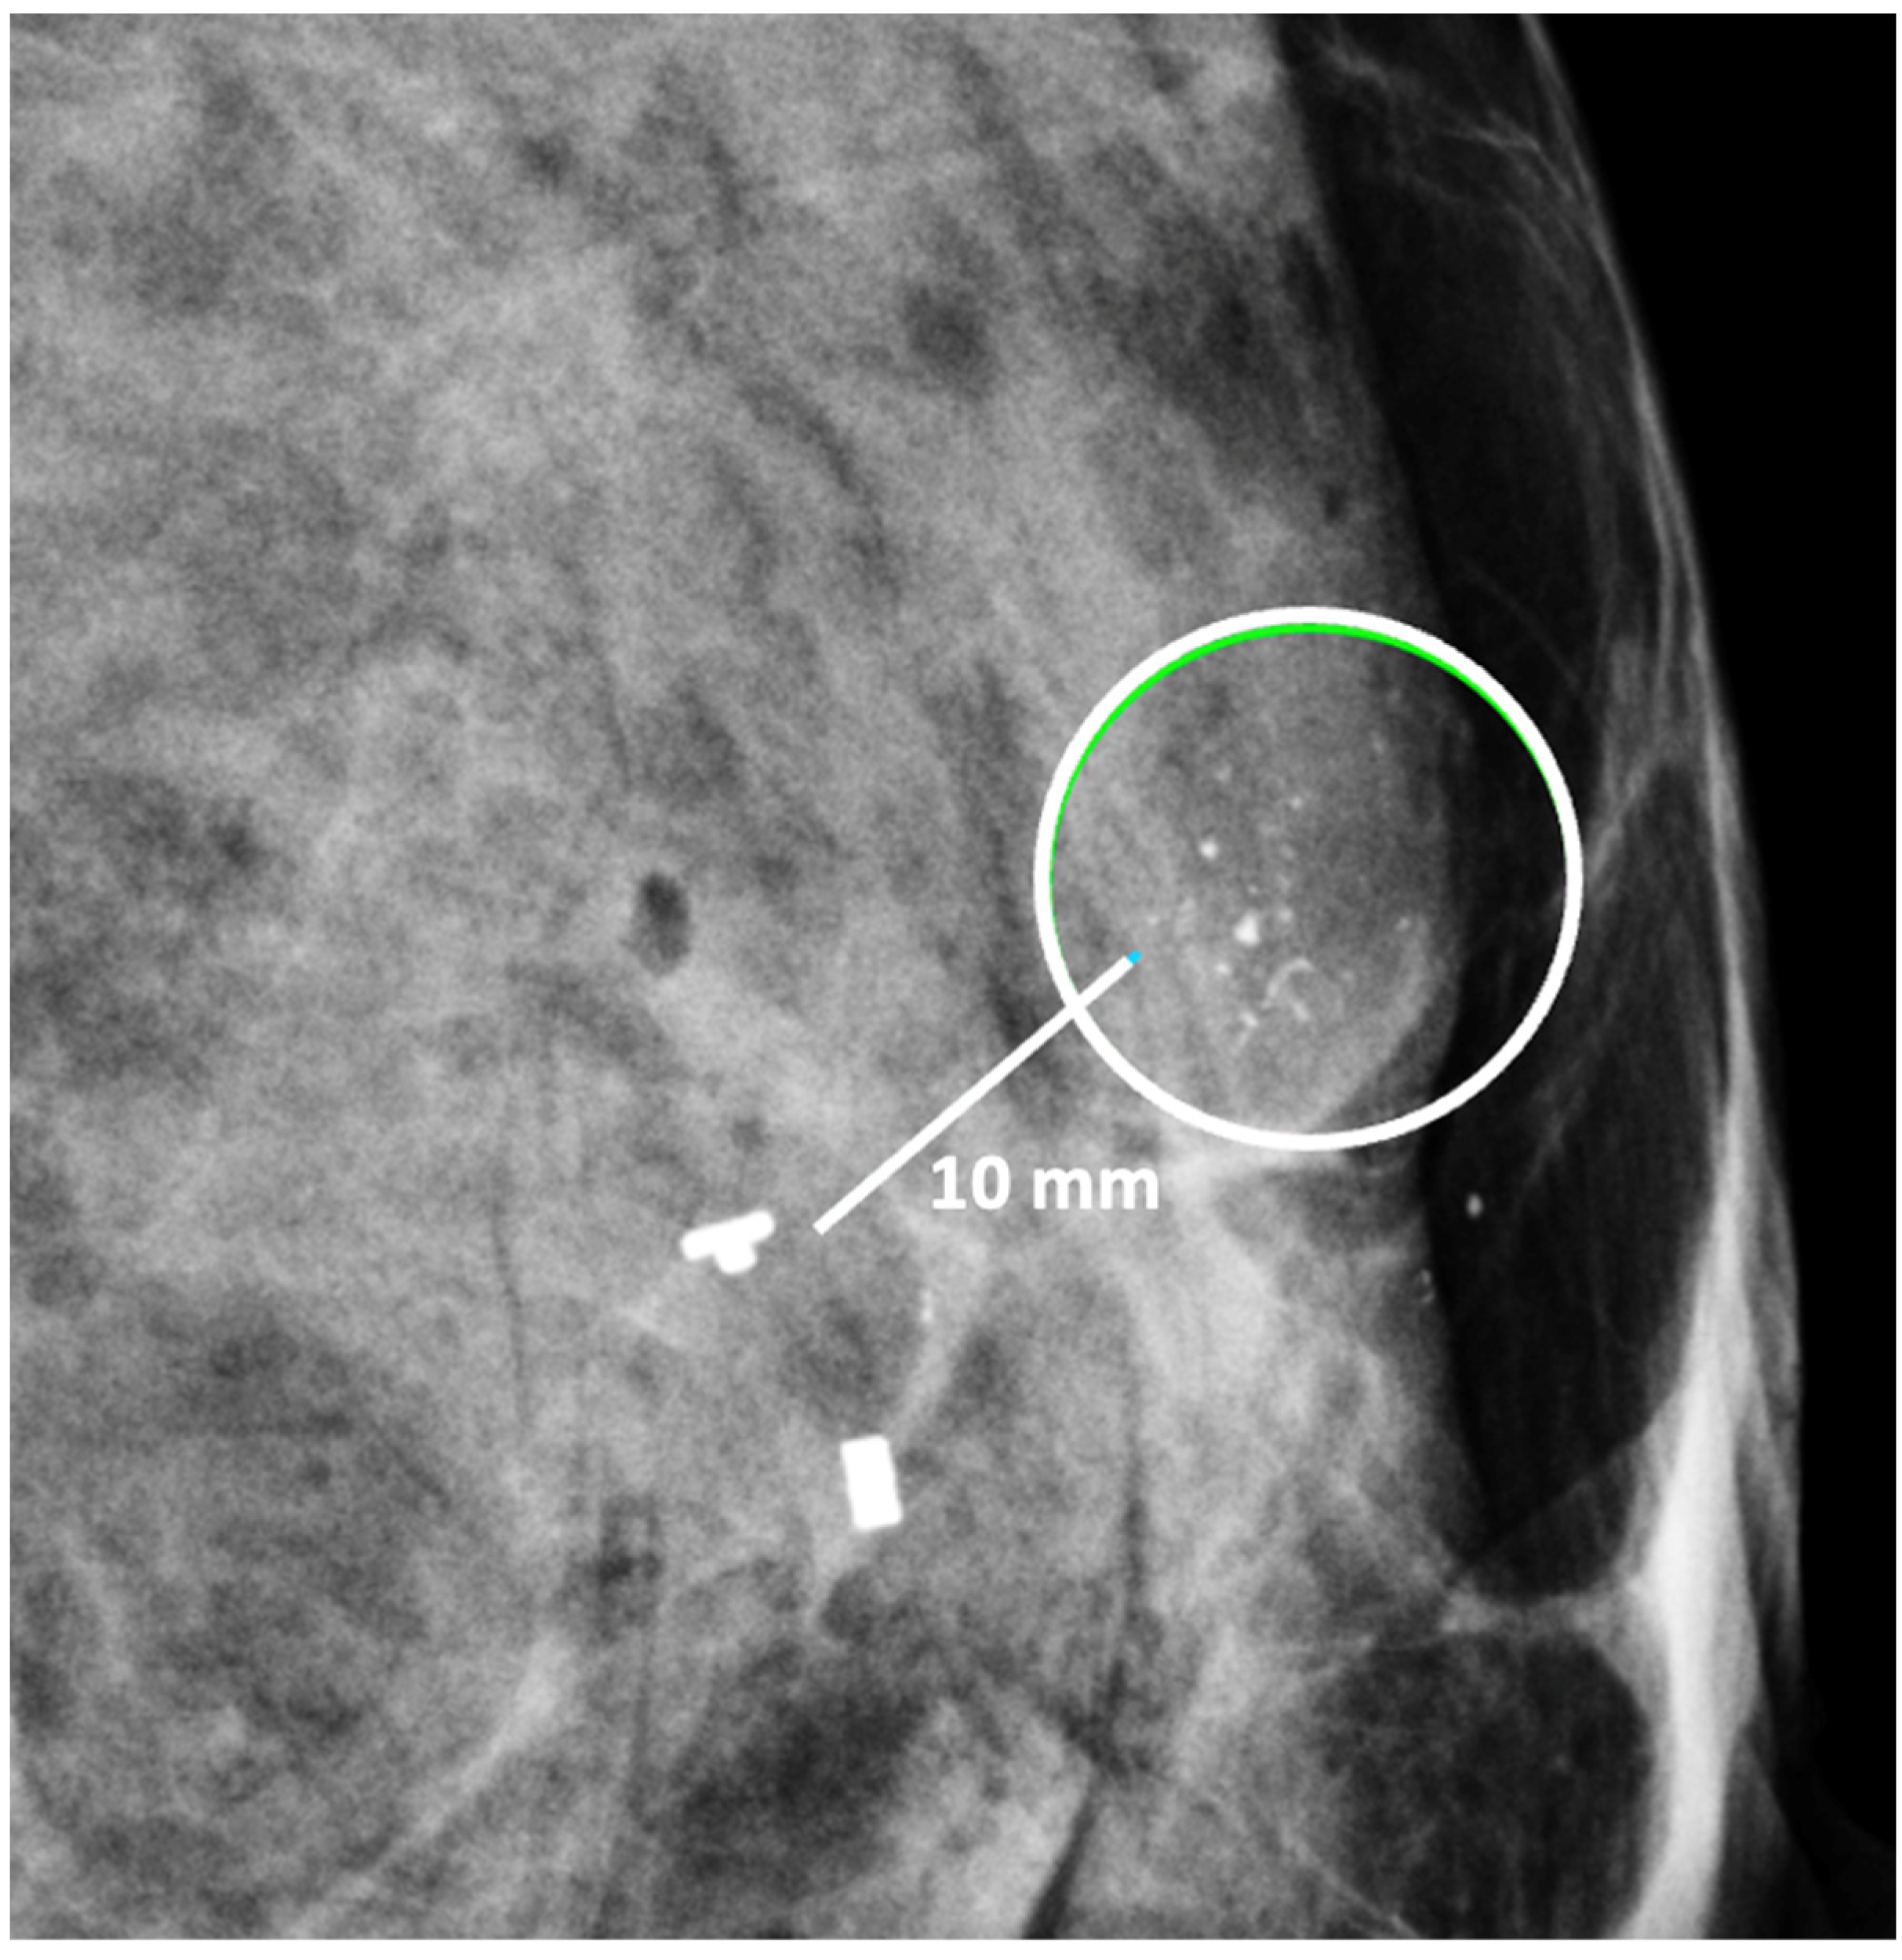

Contrast-Enhanced Breast MRI. Contrast enhanced breast MRI improves assessment of disease extent, including detection of spiculations, multifocal, multicentric, or contralateral disease, which might impact eligibility for cryoablation or alter the overall treatment plan (Figure 4). Contrast-enhanced breast MRI has the added value of permitting 3-D image reconstruction to permit viewing of the tumor from various angles for a more comprehensive assessment of tumor shape and size. Breast MRI for cancer evaluation requires the use of an intravenous contrast containing gadolinium that can be safely administered with minimal short-term and long-term risks. However, patients unwilling or unable to receive gadolinium might be able to access dedicated breast-only diffusion weighted MRI, which has limited availability in the U.S.

Figure 4.

Contrast-enhanced breast MRI image showing multifocal disease indicated by mass-like enhancement of dominant mass (indicated by single arrow and encircled with hash marks) as well as mass-like enhancement of a second focus of disease (indicated by double arrows and encircled with hash marks). The second focus was mammographically-occult.